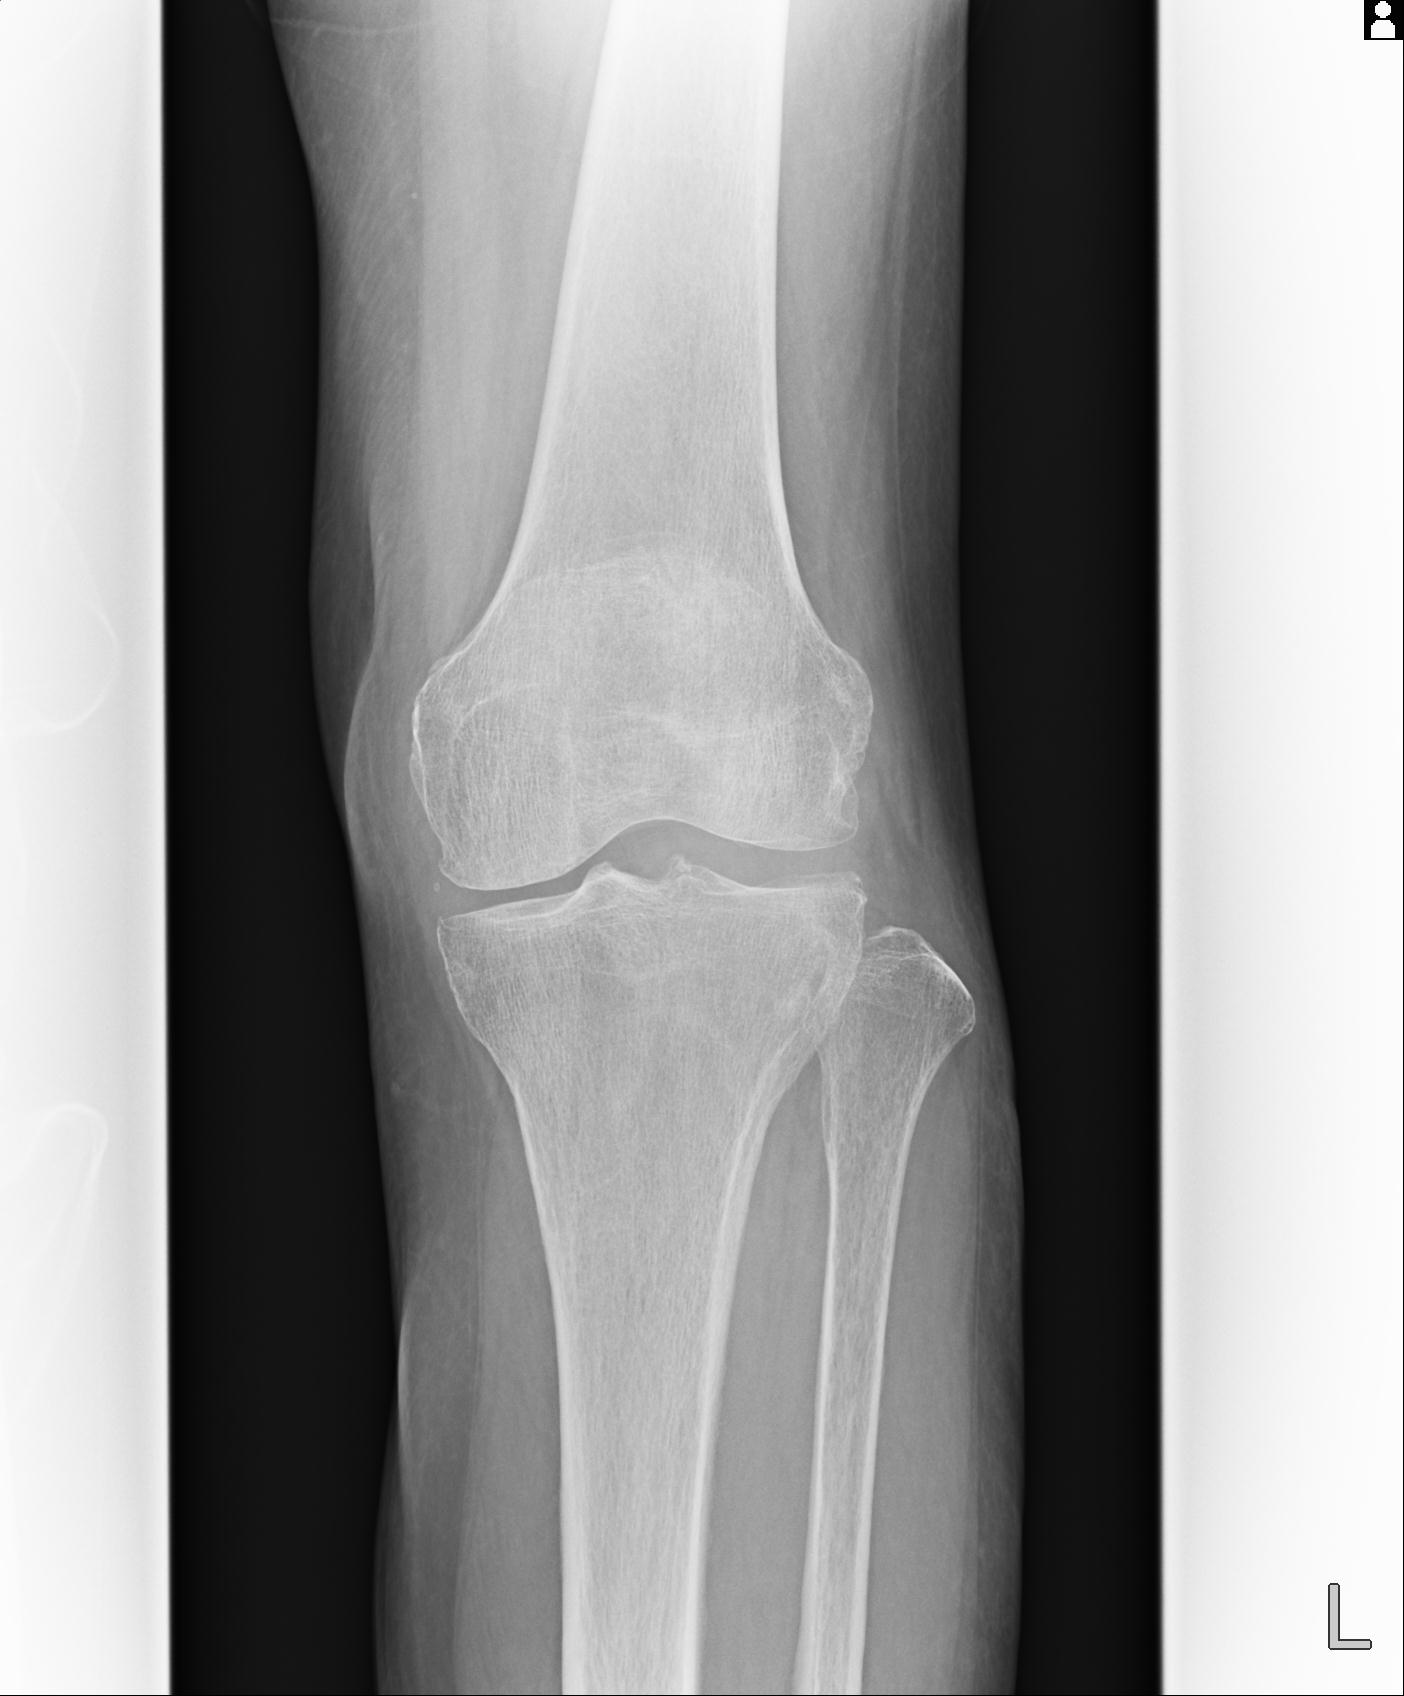

91983 11/16 左膝 2R 11/18 2R 55歳男性 脛骨骨切り術